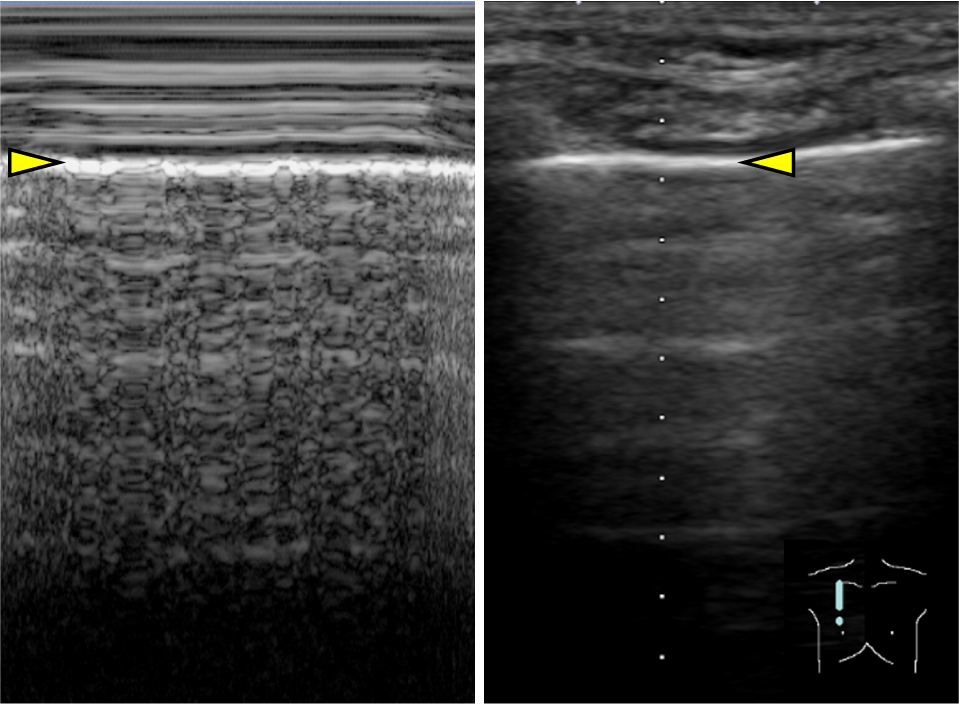

5)Seashore sign, stratosphere sign/barcode sign(Mモード)Mモードを用いて,肺の動きを表した所見である.胸膜ラインより浅部の軟部組織は動きがほとんどないため,線状の画像を呈し,海の波(sea)のように見える.胸膜ラインより深部は呼吸により動くため,ノイズによって砂浜(shore)のように見える.胸膜ラインを境目に海と砂浜のように描かれるためseashore signと呼ばれる(Fig.7).一方で気胸があると,胸膜直下の空気に動きがないため胸膜ラインでの境目がなくなり,薄い層が連なっているように見える.これを空気が層状に重なる成層圏(stratosphere)に例えて,stratosphere sign/barcode signと呼ぶ.

カーソルは胸膜に合わせる.胸膜ライン(黄色矢頭)より浅部は線状を呈し,胸膜ライン(黄色矢頭)より深部はノイズとなる.胸膜ラインを境目に海と砂浜のように描かれる.

気胸を診断するための超音波検査では,仰臥位の患者の第2–3肋間鎖骨中線にプローブを置き,bat signを描出する.Lung slidingの消失(Movie 3),B lineの消失,lung pulseの消失,またはlung pointの存在(Movie 4)を総合してプローブを当てた領域の気胸を診断する(各用語はTable 1を参照).また,診断の補助としてMモード画像所見(Fig.10)も気胸診断の根拠となるため,特に小児では積極的に使用して良いだろう.

胸膜上は呼吸性変動が極めて少ないため直線状となる.一方,胸膜下は,正常肺では呼吸性変動により頼粒状に,気胸では呼吸性変動がないため直線状となる.前者は海岸の砂浜になぞらえてseashore sign,後者はstratosphere signまたはbarcode signと呼ばれる.